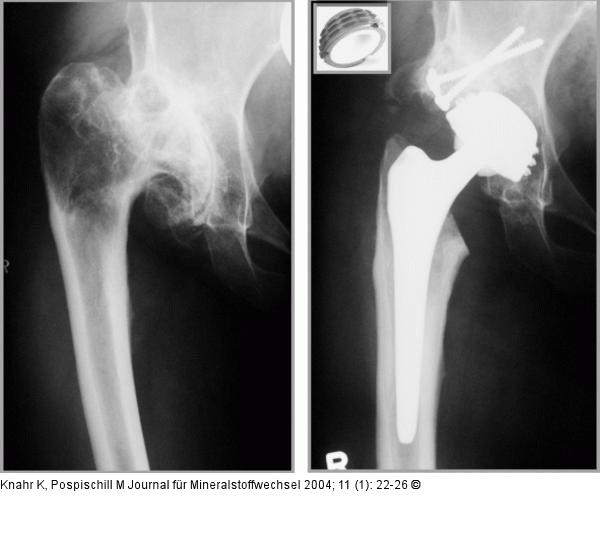

Abbildung 5: Hüftgelenk Implantation einer hochvernetzten Polyäthylen-Metall-Gleitpaarung bei 55jähriger Patientin mit hochgradiger Dysplasiecoxarthrose |

Implantation einer hochvernetzten Polyäthylen-Metall-Gleitpaarung bei 55jähriger Patientin mit hochgradiger Dysplasiecoxarthrose |